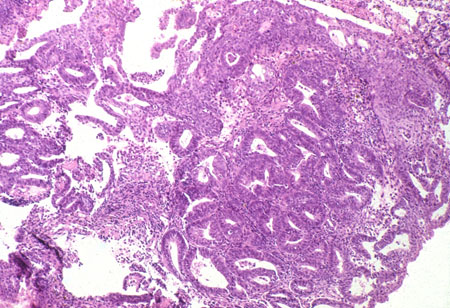

Carcinoma endometrioide do corpo uterino: o subtipo mais comum de câncer do endométrio, presente em até 90% dos casos, com a histologia mostrando glândulas malignas reconhecíveis e células glandulares nas formas mais bem diferenciadas (baixo grau)[4]

[Figure caption and citation for the preceding image starts]: Subtipo histológico: adenocarcinoma endometrial endometrioide, o subtipo mais comum; diagnosticado em dilatação e curetagem em uma paciente que apresenta sangramento pós-menopausa (fotomicrografia, coloração de hematoxilina e eosina)Cortesia do Professor Robert H. Young, Departamento de Patologia, Massachusetts General Hospital [Citation ends].

Grau 1 (G1): padrão de crescimento sólido não escamoso ou não morular de ≤5%[Figure caption and citation for the preceding image starts]: Adenocarcinoma endometrioide de grau 1 ou de baixo grau (direita) com um histórico de endométrio proliferativo (esquerda); (fotomicrografia, coloração de hematoxilina e eosina)Cortesia do Professor Robert H. Young, Departamento de Patologia, Massachusetts General Hospital [Citation ends].